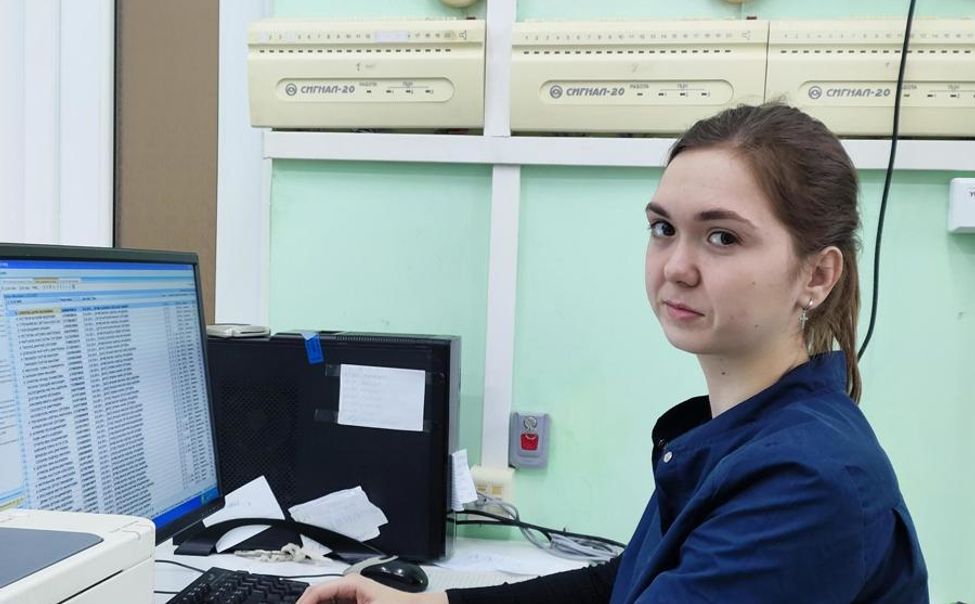

Благодаря целевому обучению ежегодно коллектив Шумерлинского медицинского центра пополняется молодыми специалистами.

Санитарная авиационная служба дважды перевозила пациентов из Шумерлинского медицинского центра в столицу Чувашии. В обоих случаях диагностирован острый инфаркт миокарда.

14 сентября мобильная бригада специалистов республиканских клиник отправилась в Шумерлинский муниципальный округ.

Прокуратура провела в Шумерлинском округе проверку исполнения законодательства об охране здоровья граждан и санитарно-эпидемиологическом благополучии населения.